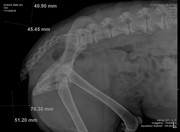

Добавлено (12.11.2018, 20:37) --------------------------------------------- Сил нет писать. Просто нет ни каких моральных сил. Нужно дойти до стадии принятия и жить дальше. Вот, что я узнала. при ортопедическом осмотре нарушений со стороны опорнодвигательного аппарата не выявлены. ( не считая старых травм, на кануне укол получил, поэтому не хромал). Рентген делали без миорелаксанта. Не хотела его "нагругжать". По ним вроде, тоже с суставами все ок. Есть подозрение на грыжу в отделе между последним кресцовым и первым хвостовым. Анализ мочи в норме, кроме кислой среды. На узи нашли наше старое новообразование. Оно немного меньше (на пол см.) . При ректальном осмотре простата совсем маленькая (около 1 см) (это потому что мы его кастрировали) Самое плохое, что на рентгене мы нашли еще одно новообразование. Оно давит и на мочевой и на кишечник и может быть причиной болей. С сегодняшнего дня у Цезаря подтекает моча. Если лежит на одном месте пару часов, лужа 20 см.образуется. Какал раньше 3 раза в день. Сейчас 1 раз. На сегодняшний день, колю мелбек и мильгамму. Аппетит хороший, бегает, по лестнице ходит. Если НПВС обезбаливает - это точно боль связанная с нервом, а не с новообразованием. Возможно он передавлен. Я пока не придумала, что делать???? Вообще..... Я точно знаю, что хочу как можно меньше страданий ему принести и переживаний. Он все эти клиники переносит с таким стрессом. Я хочу любить его и баловать. Но в то же время - я врач - и сидеть сложа руки не могу. Вот что я прошу! 1) может возможно снимки показать заочно Строку или еще кому-то в МИнске, послушать их! 2) если решать обезболивать, я за трококсил. Т.к. уезжаю и не смогу контролировать процесс. 3) дайте совет, кто сталкивался с подтеканием, с запорами из-за уменьшения просвета кишечника. Как вы справляетесь? Памперсы? Или что-то можно придумать? 4) Хочу услышать много мнений и все переварить. Но пока вот что я думаю. Цезарь мой родной человек. ТО есть лучше человека. И я не хочу последние его месяцы мучать , оставлять одного. Мне сейчас написали врачи - однозначно оперировать! Передавливает кишечник и может быть поздно.Но я не знаю.... я не хочу чтобы он умер на операционном столе или чтобы после операции было еще хуже. Я прошу совета!!!!!